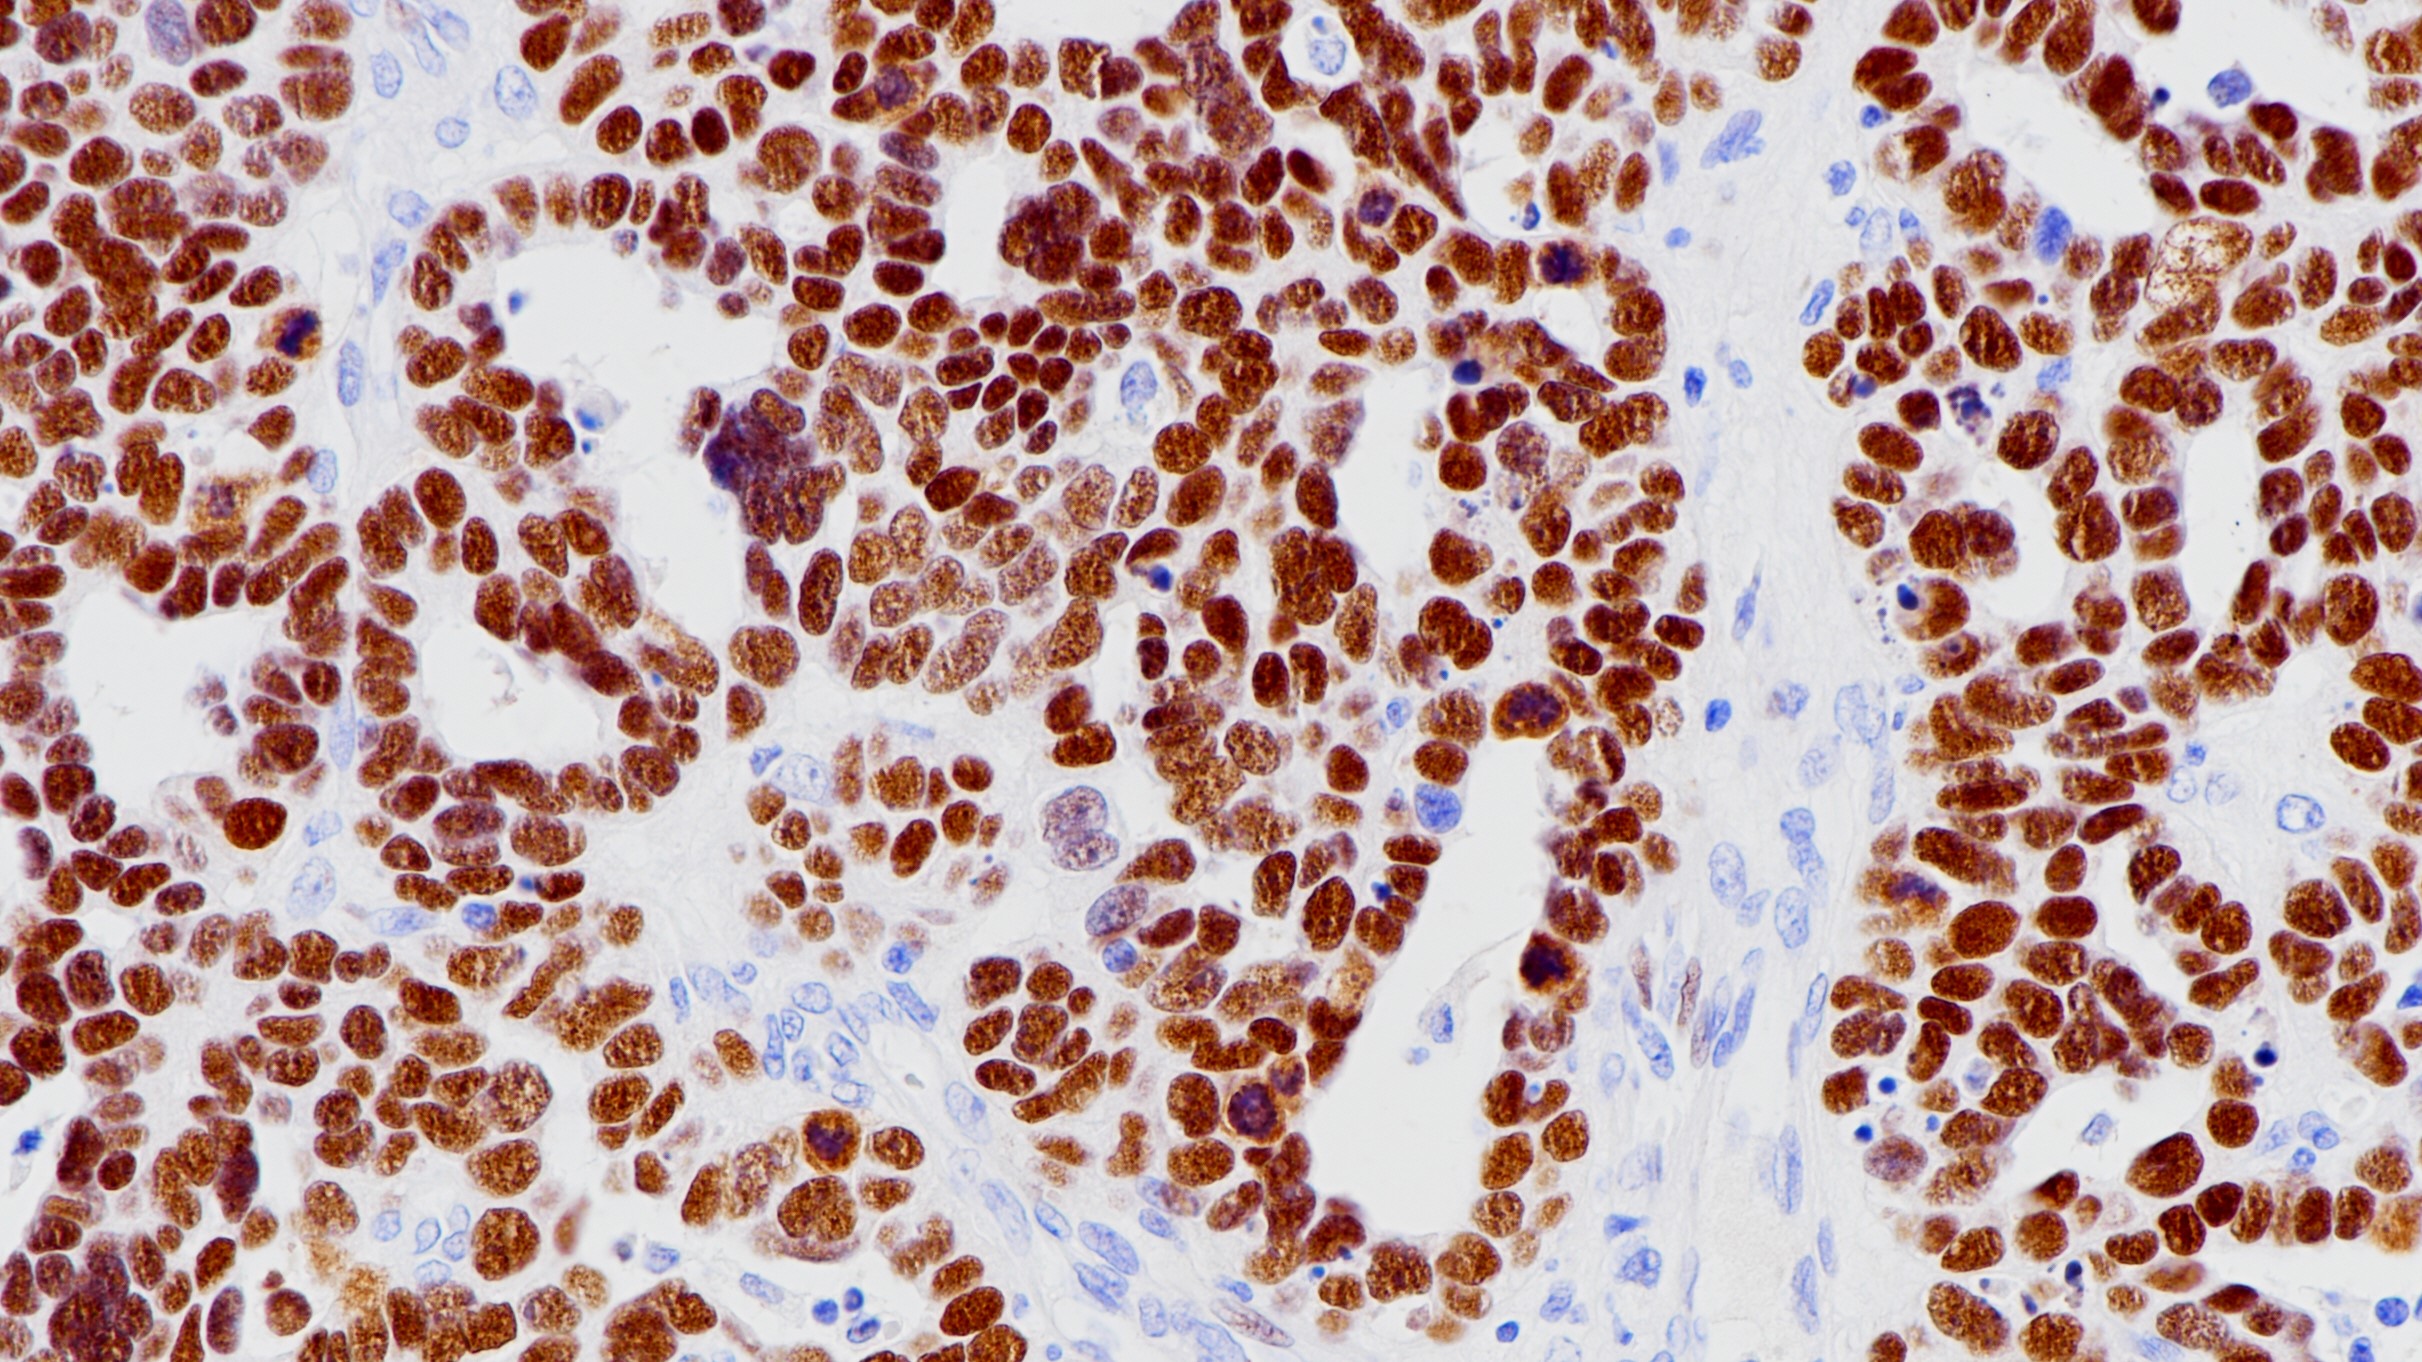

WT1作为转录因子,在泌尿生殖系统的发育过程中起到重要作用。正常上皮细胞中,WT1主要在输卵管和卵巢表面的上皮细胞表达,而在子宫内膜和宫颈的上皮细胞不表达。非上皮细胞中,WT1在间皮基质细胞、女性生殖道的基质细胞、睾丸的非生殖细胞以及肾脏的足细胞中表达。肿瘤组织中,WT1主要在Wilm’s瘤和间皮瘤中表达,浆液性卵巢癌和一些乳腺癌中也有表达,在临床上可用来鉴别恶性间皮瘤和浆液性卵巢癌。

卵巢癌